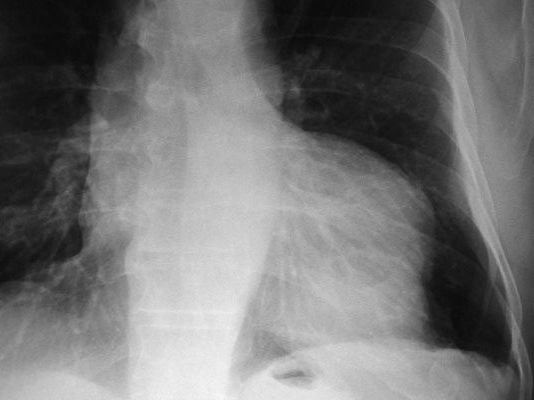

Fibrosis pulmonar. ICC.

Neumonia basal derecha.

Neumonía basal derecha.

Neumonía basal.